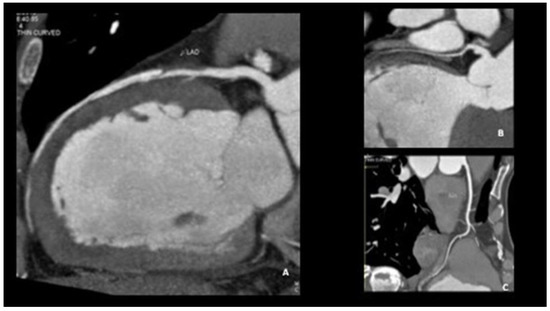

Chronic or Changeable Infarct Size after Spontaneous Coronary Artery Dissection

by Gordana Krljanac, Svetlana Apostolovic, Zlatko Mehmedbegovic, Olga Nedeljkovic-Arsenovic, Ruzica Maksimovic, Ivan Ilic, Aleksandra Djokovic, Lidija Savic, Ratko Lasica and Milika Asanin

Diagnostics 2023, 13(9), 1518; https://doi.org/10.3390/diagnostics13091518 - 23 Apr 2023

Spontaneous coronary artery dissection (SCAD) could be the cause of acute myocardial infarction (AMI) and sudden cardiac death. Clinical presentations can vary considerably, but the most common is the elevation of cardiac biomarkers associated with chest discomfort. Different pathological etiology in comparison with [...] Read more.

Spontaneous coronary artery dissection (SCAD) could be the cause of acute myocardial infarction (AMI) and sudden cardiac death. Clinical presentations can vary considerably, but the most common is the elevation of cardiac biomarkers associated with chest discomfort. Different pathological etiology in comparison with Type 1 AMI is the underlying infarct size in this population. A 42-year-old previously healthy woman presented with SCAD. Detailed diagnostical processing and treatment which were performed could not prevent myocardial injury. The catheterization laboratory was the initial place for the establishment of a diagnosis and proper management. The management process can be very fast and sometimes additional imaging methods are necessary. Finding predictors of SCAD recurrence is challenging, as well as predictors of the resulting infarct scar size. Patients with recurrent clinical symptoms of chest pain, ST elevation, and complication represent a special group of interest. Therapeutic approaches for SCAD range from the ”watch and wait” method to complete revascularization with the implantation of one or more stents or aortocoronary bypass grafting. The infarct size could be balanced through the correct therapeutical approach, and, proper multimodality imaging would be helpful in the assessment of infarct size. Full article